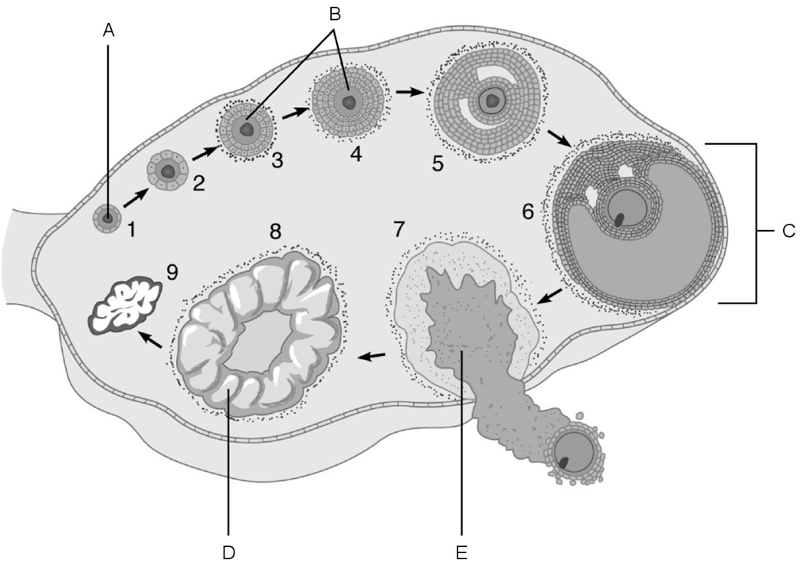

Afferent arteriole.

A

Cells that are most affected by ADH.

C

Cells that are the most active in reabsorbing the filtrate.

E

Medulla of the kidney.

E

Glomerulus.

C

Is composed of simple squamous epithelium.

A

Proximal convoluted tubule.

Site at which most of the tubular reabsorption occurs

Glomerulus.

Site of filtrate formation.

Peritubular capillaries.

Blood supply that directly receives substances from the tubular cells.

Collecting duct.

Site that drains distal convoluted tubule